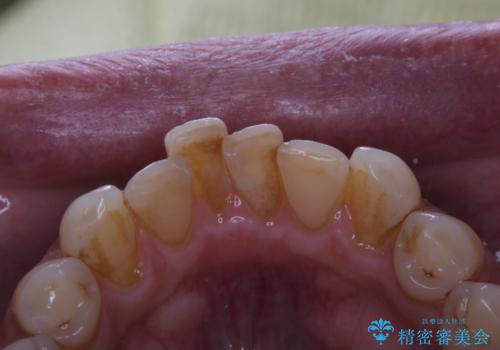

- インビザラインでの矯正治療中の方です。コーヒーをよく飲むため、着色が気になるとのことでした。PMTC60分コースを行いました。

PMTC(保険外治療)は、毎日の歯磨きで落としきれない汚れや、コーヒ、紅茶・タバコのヤニなどの着色も除去します。目には見えない歯と歯の間・歯肉の境目・インビザライン中はアタッチメント周囲などに残っているプラーク(歯垢)もしっかり取り除きます。PMTCでは専門的な機械や材料を使用して、徹底的に汚れを除去するため、虫歯・歯周病・口臭予防などにつながります。